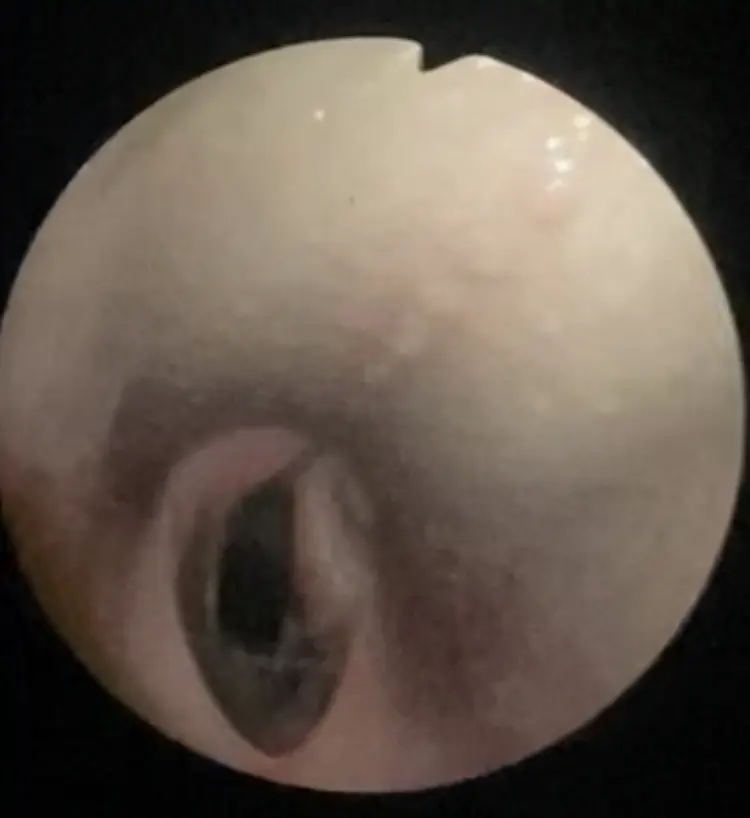

Advanced Diagnostic Imaging

We carry out diagnostic tests such as scintigraphy, magnetic resonance imaging, among others, in collaboration with equine veterinary hospitals.